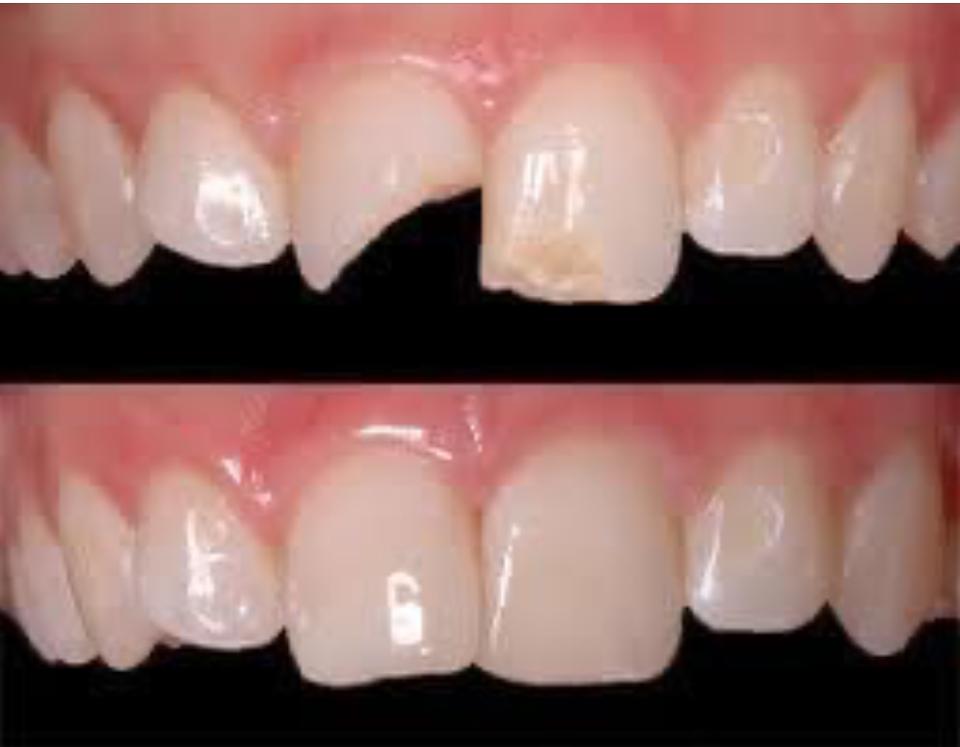

La ricostruzione in composito di un dente fratturato coronalmente è una procedura odontoiatrica mirata a riparare un dente danneggiato nella sua parte visibile (la corona) utilizzando un materiale estetico e durevole chiamato composito. Questo tipo di intervento è spesso indicato quando un dente è scheggiato, rotto o presenta una frattura che non coinvolge in modo esteso la radice o il tessuto sottostante.